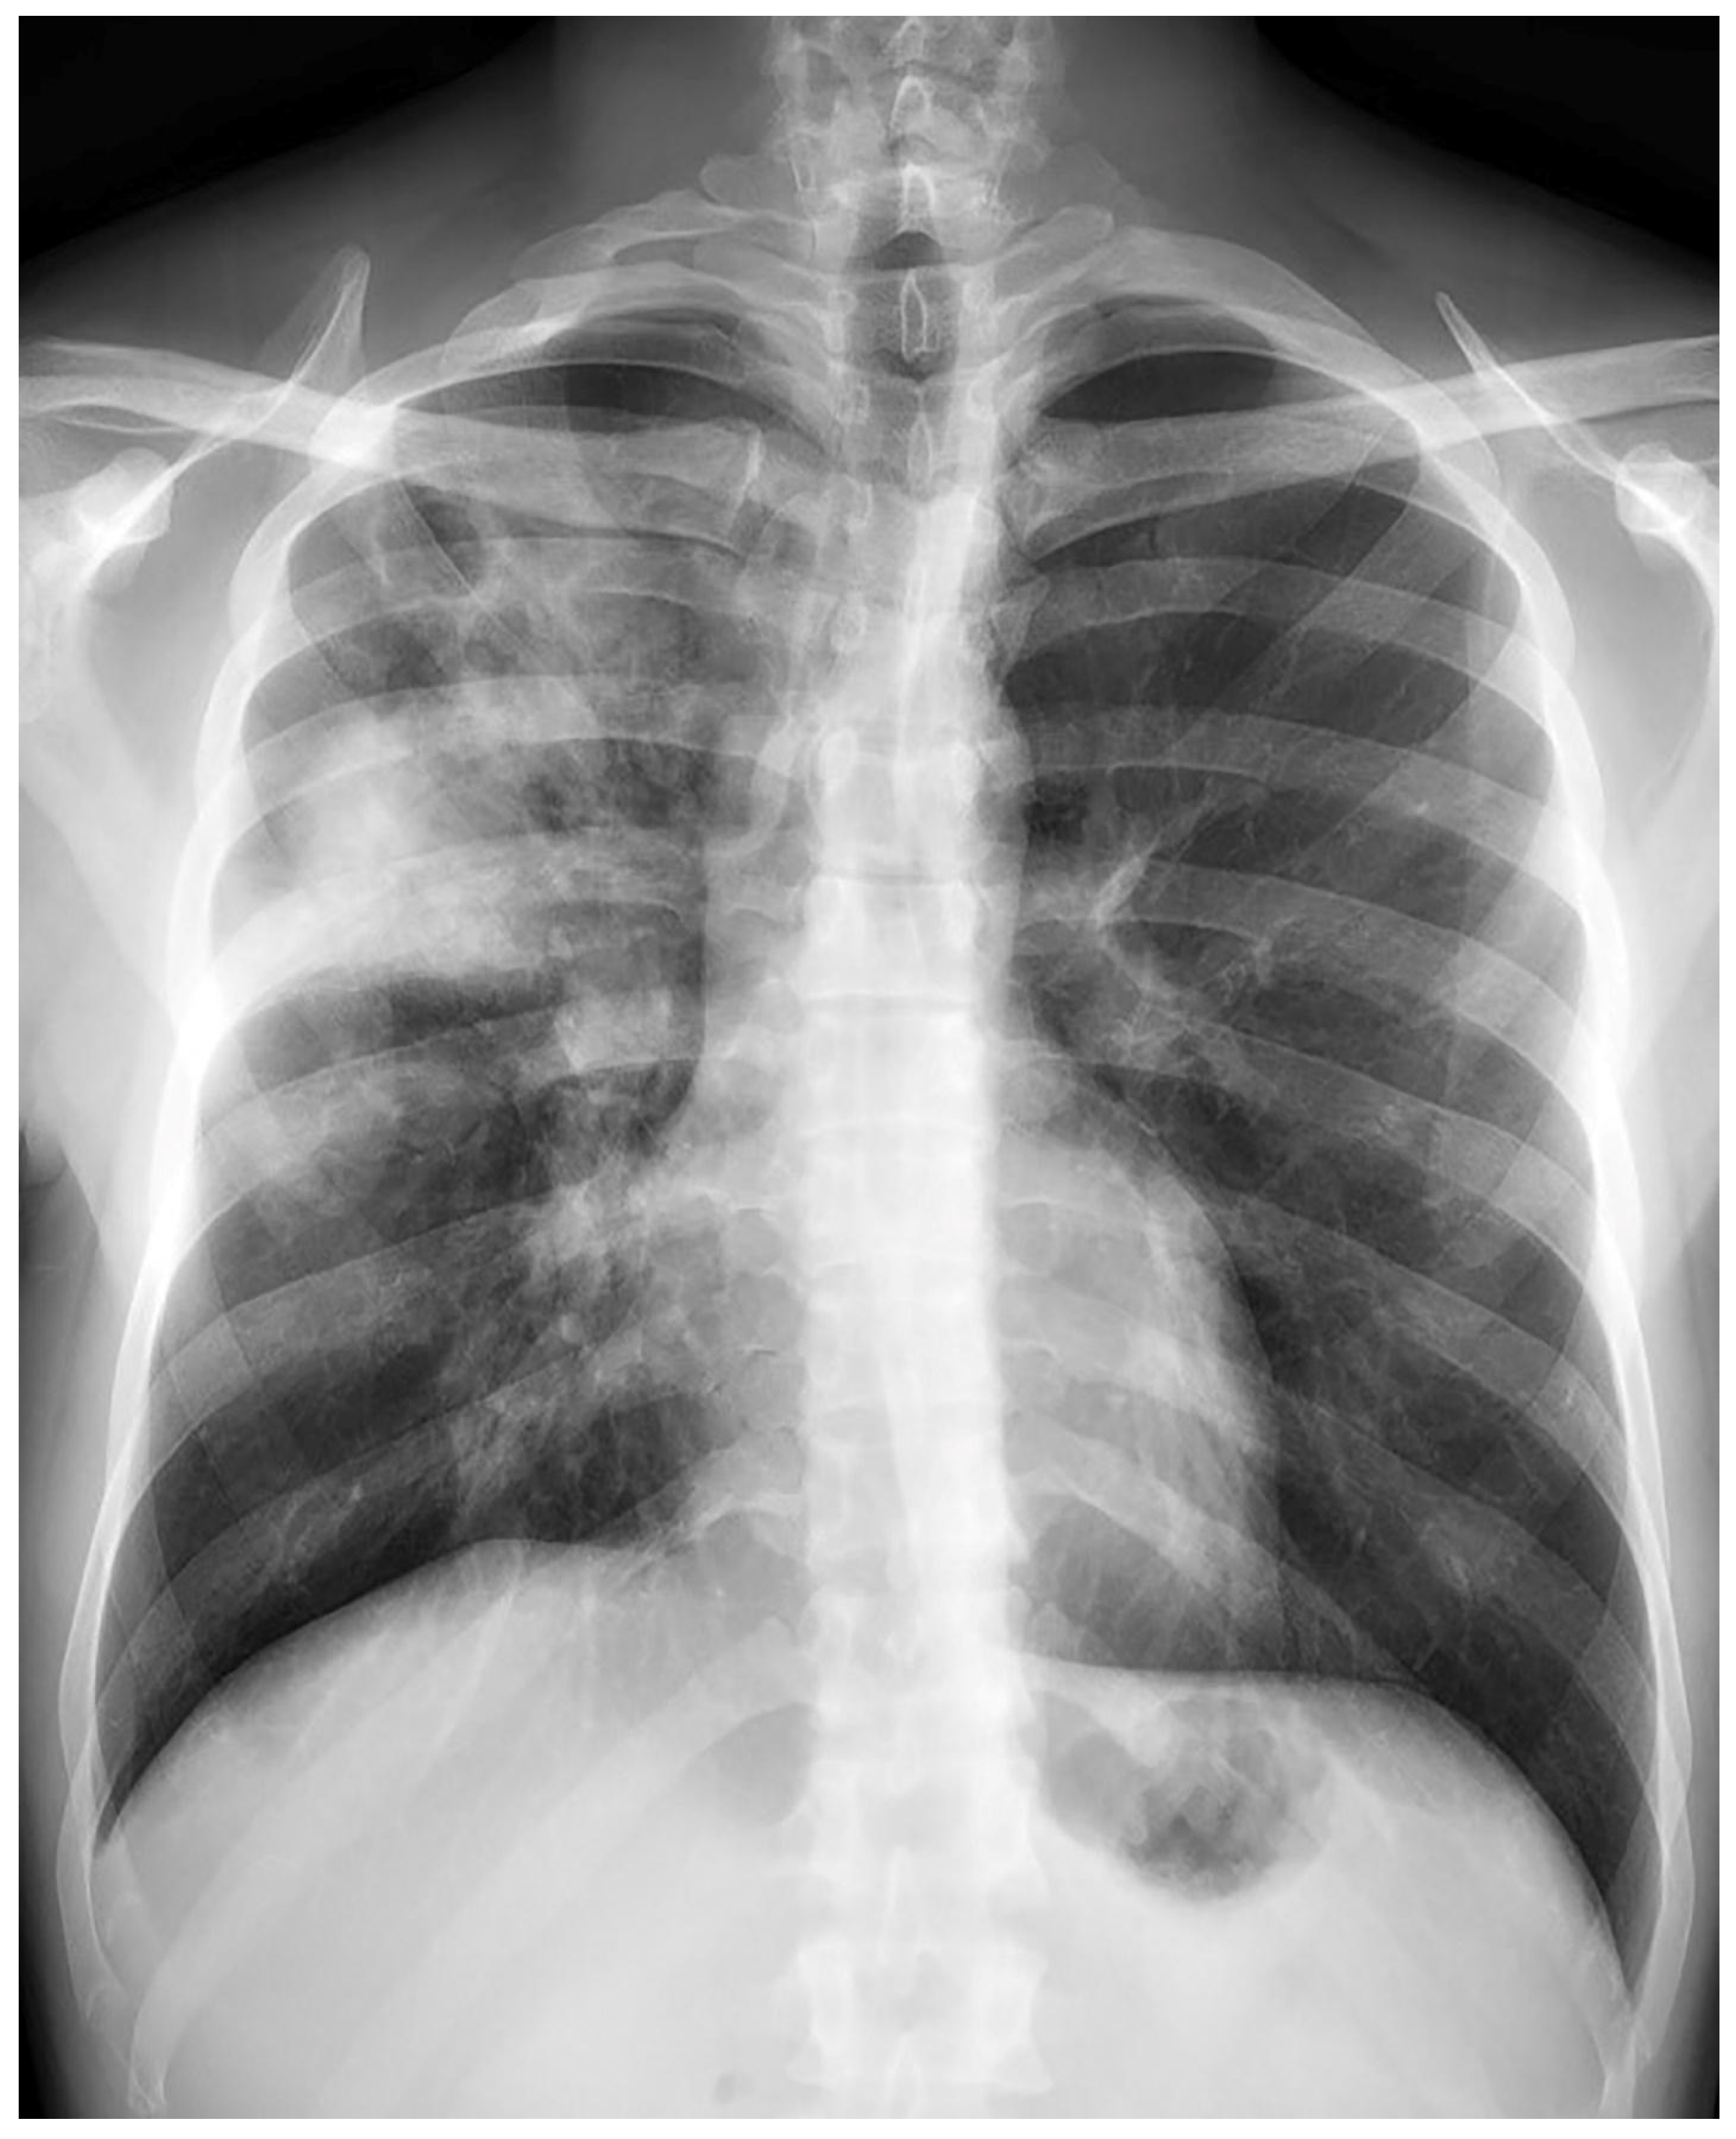

Treatment results of seven patients were reported as follows; two patients as not evaluated (returned to their home country), two patients as completion of treatment, and three patients as cured. The duration of treatments was planned as nine months, and the treatment of the patient with FQ and Z resistance (case 7) continued for 12 months. No recurrence was detected in the first-year follow-up of the five patients who could be followed. Regarding Case 4’s chest X-ray images at the beginning and the 59th day of the treatment (Figure 1 and Figure 2) and Case 7’s chest X-ray images at the beginning and the 12th month of the treatment (Figure 3 and Figure 4) a significant radiological improvement was observed.

Figure 4. Case 7, 12th month of the treatment.